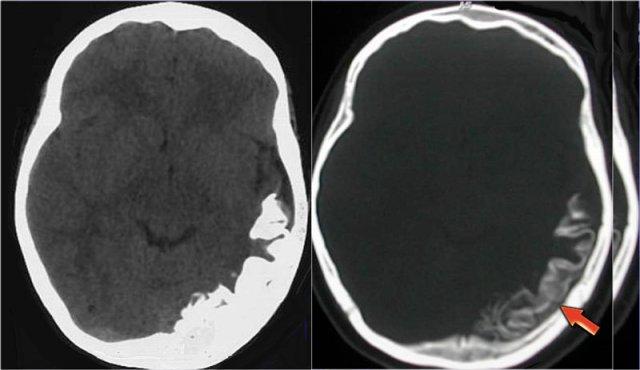

Một người đi xe đạp 46 tuổi nhập viện với triệu chứng co giật sau khi bị xe ô tô đâm.

Hình ảnh CT chỉ cho thấy xuất huyết dưới nhện tối thiểu (mũi tên).

MRI được thực hiện vài tuần sau chấn thương do bệnh nhân có thay đổi nhân cách.

Chuỗi xung T2* cho thấy nhiều ổ lắng đọng hemosiderin tại vùng ranh giới giữa chất xám và chất trắng, phù hợp với tổn thương sợi trục lan tỏa (DAI).

Lưu ý vị trí của các vi xuất huyết này khác với các ổ xuất huyết CAA nằm ở ngoại vi.